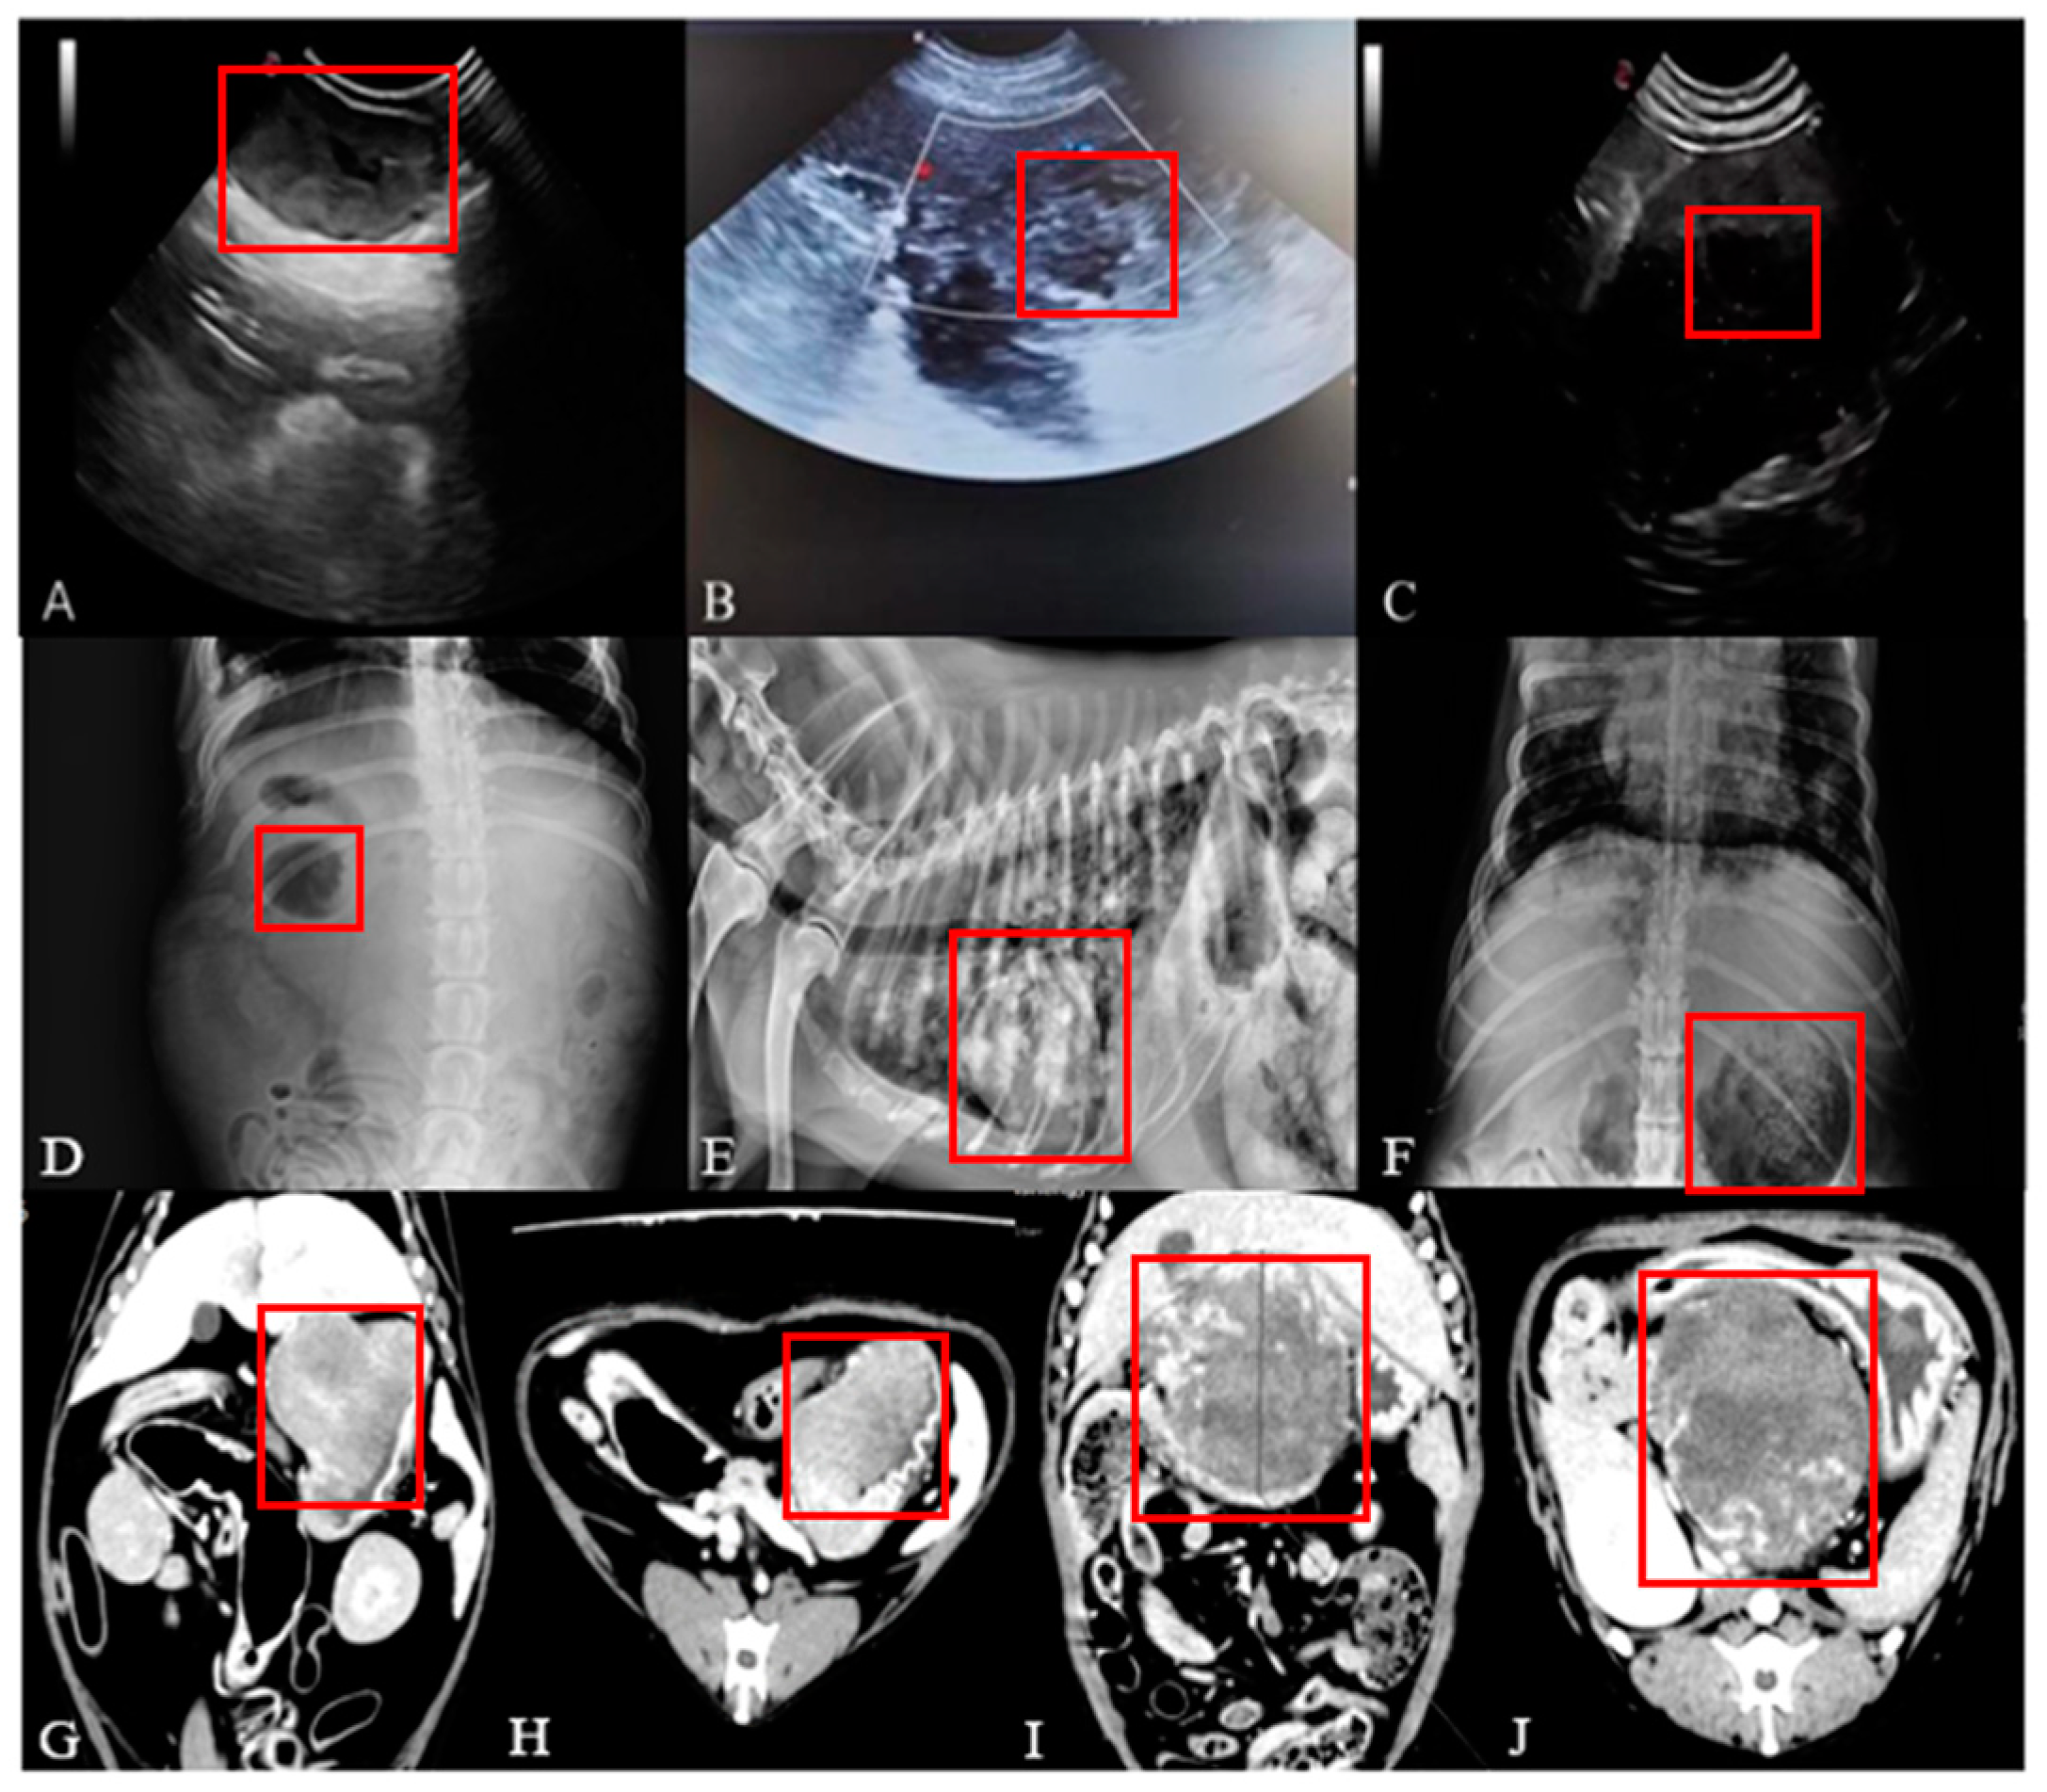

2.3. Imaging Examination

3.2. Imaging Examination